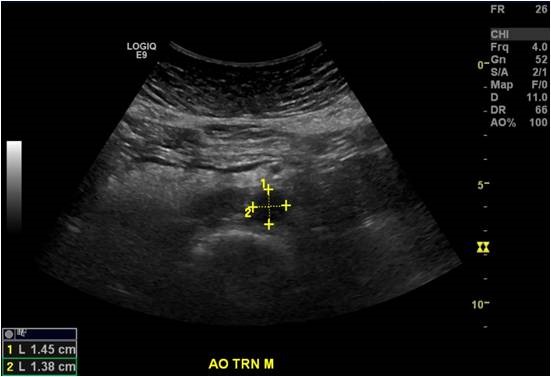

Abdominal Aortic Ultrasound Examination

When the sonographer assesses the large artery in the abdomen that carries blood from the heart through the abdomen and into the legs with diagnostic ultrasound. Diameter measurements are taken to screen for a dilatation in the vessel wall, also known as an aneurysm or for follow up on a patient with a known abdominal aortic aneurysm.

Abdominal Aortic Ultrasound Image

Screening for Abdominal Aortic Aneurysm

An abdominal aortic aneurysm (AAA) is when the wall of the aorta weakens and bulges out. Treatment of the aneurysm will depend on the size of the aneurysm. Medicare Part B will cover a one-time AAA screening ultrasound examination if you have a family history an AAA. You may also qualify if you are a male ages 65 - 75 years old and have smoked at least 100 cigarettes in your lifetime. An AAA is less common in women who have never smoked. Patients will need a referral from their doctor for this exam.